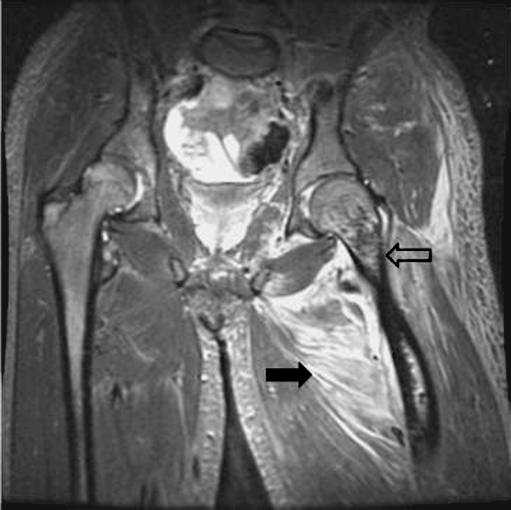

After stabilization, MRI of the pelvis and thighs showed extensive thrombosis of the left common femoral vein extending into intramuscular branches of the upper thigh, a 1-cm fluid collection deep within the vastus intermedius, and heterogenous signal within the intramedullary compartment of the shaft and neck of the femur indicative of intraosseous gas secondary to osteomyelitis (Fig. 5).

Fig. 5.

MRI of the pelvis and thighs extensive soft tissue edema (black arrow) and heterogeneous signal within the intramedullary compartment of the shaft and neck of the femur indicative of intraosseous gas secondary to osteomyelitis (gray arrow)